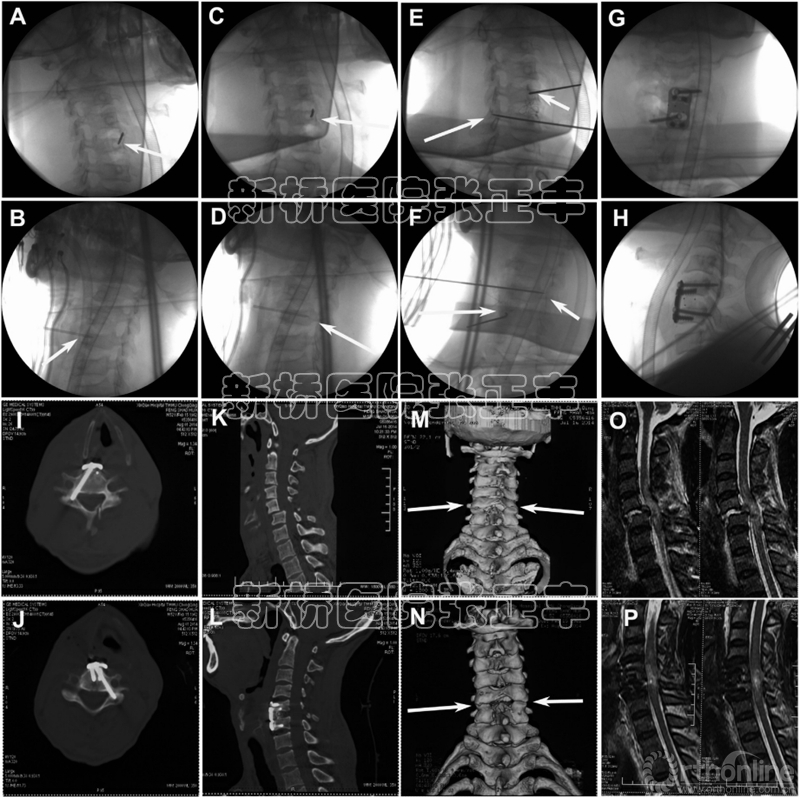

第二,椎弓根影像的皮质圆形区域中心即为进针点,通常距离上终板大约2毫米,位于椎体的中心附近(Fig. 1A)。对侧斜位片确定头尾侧倾斜角度(Fig. 1B)。钉道是由一个1.7 mm的开口器创建。

第三,根据明确的矢状面和冠状面倾斜角度,开口器插入到椎体后缘(通常1.7厘米),在斜位片上要位于椎弓根的圆形区域内(Fig. 1C,D)。

第四,1.5 mm克氏针电转插入,并椎弓根内转入。利用正侧位、椎弓根轴线视图透视反复确认(Fig.1E,F)。在插入1毫米的导针后,由一个空心圆锥进行攻丝(3.5毫米)。

最后,选择合适长度的颈椎椎弓根螺钉钢板(Z3)(Fig. 1G,H)。该钢板可用于APS和椎体螺钉以对抗旋转。椎弓根螺钉的直径为4毫米,长度范围为30、32、34毫米。椎体螺钉的直径为4毫米,长度范围从14、16毫米(Fig. 2)。

术后,戴颈托用来保护病人的脖子6个星期。术后通过CT扫描(1mm层厚)来检查椎弓根螺钉置入的准确性 (Fig. 1I,J)。

Fig. 1.C5-C6双侧小关节脱位(Case 3)APS植入的图像。(A)斜位片显示术中开口器插在C5椎弓根圆圈(箭头)。(B)对侧斜位片确认头倾或尾倾角度(箭头)。(C, D)术中斜位X线片显示和确认开口器到椎体后缘(箭头)。(E, F)术中斜位片显示导丝插入C5-C6椎弓根(箭头)。(G, H)术中透视图像显示C5-C6钢板螺钉固定后。(I, J)术后CT显示前路椎弓根螺钉在C5和C6的位置良好。(K, L)术前和术后的矢状位CT显示C5–C6脱位复位。(M, N)术前和术后的CT三维重建显示精确的C5–C6脱位复位(箭头)。(O, P)术前和术后MRI显示脊髓T2矢状位图像的压迫和解压。

术后X线、MRI和CT显示颈椎序列良好,椎弓根螺钉准确置入椎弓根皮质内(Fig. 1K–P, Fig.3)。患者随访时间6个月以上,X线平片及CT扫描显示成功的脊柱融合的。没有由于技术运用而导致的并发症或内固定失败。4个ASIA A级和1个B级患者无神经功能改善;一个ASIA B级患者神经功能改善至C级;2例ASIA D级患者神经功能改善至E级;没有ASIA E级患者出现神经功能恶化。

此外,它允许从C6和C7椎体两侧插入2颗APS (Fig.3),因为C6和C7进钉点位于椎体表面的同侧[11–19]。虽然C3- C5进钉点的位于中央或对侧,每一个节段从对侧植入APS是允许的(Fig. 1K–P),这样从理论上较APS同侧固定提供了更强的抗旋转[14,15,19]。